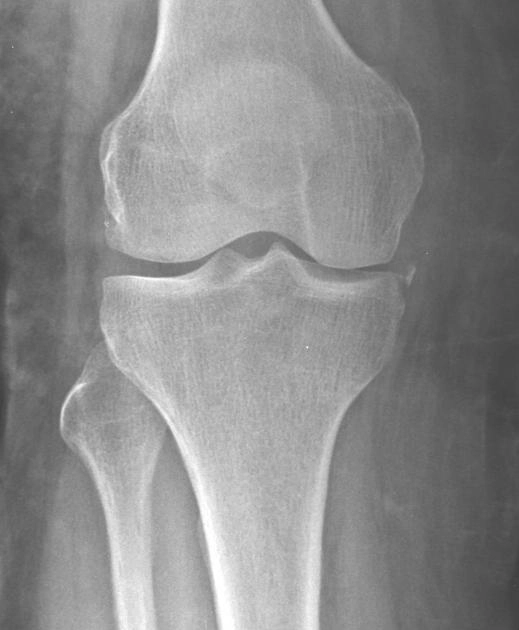

• Gãy bong khớp gối